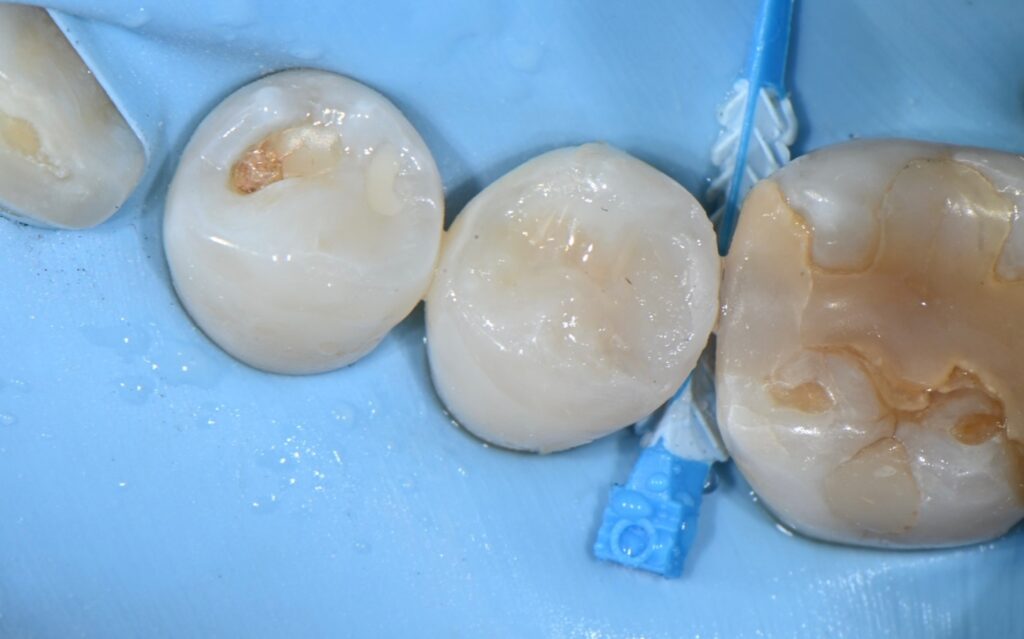

최근에는 접착을 최대한 이용하고

그리고 최소한의 치아삭제로 치아를 치료하는

레진 빌드업이라는 치료를 많이 받으시는데요

몇가지 사진을 보면서 레진빌드업의 과정과

장점에 대해서 알려드리도록 하겠습니다

앞서 보여드린 치아를 치료하는 과정입니다

빌드업치료는 이렇게 치아삭제를 최소화하고 이차충치에 강하면서

신경치료의 가능성을 줄여주는

등등 아주 여러가지 장점이 많은 치료방법입니다

충치를 제거하고 뒤쪽을 다듬은 모습입니다

정리가 그래도 깔끔하게 된듯한데

불안한 부분은 신경이 가까워서 혹시나

신경치료를 들어갈까 걱정했지만

그래도 적절히 빌드업이 가능했습니다